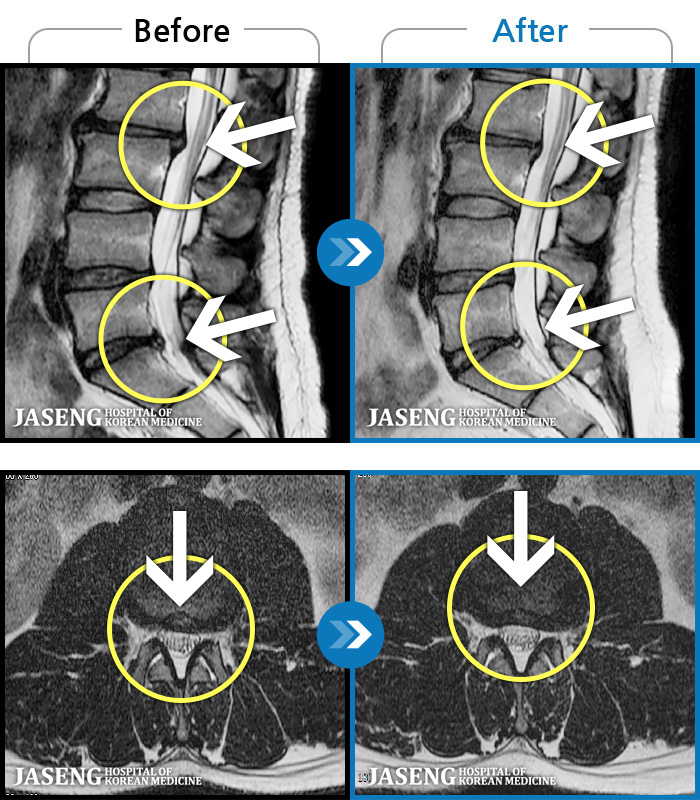

허리디스크

인천 · 강아현 원장

우측 허리 통증 및 다리 저림이 심하여 앉거나 바로 눕는 것도 힘든 상태로 내원하셨습니다. 감각 저하도 동반되어 심각한 신경손상이 의심되는 상황이었습니다.

촬영시기

2024.07.27 ~ 2025.04.05

2025.04.16